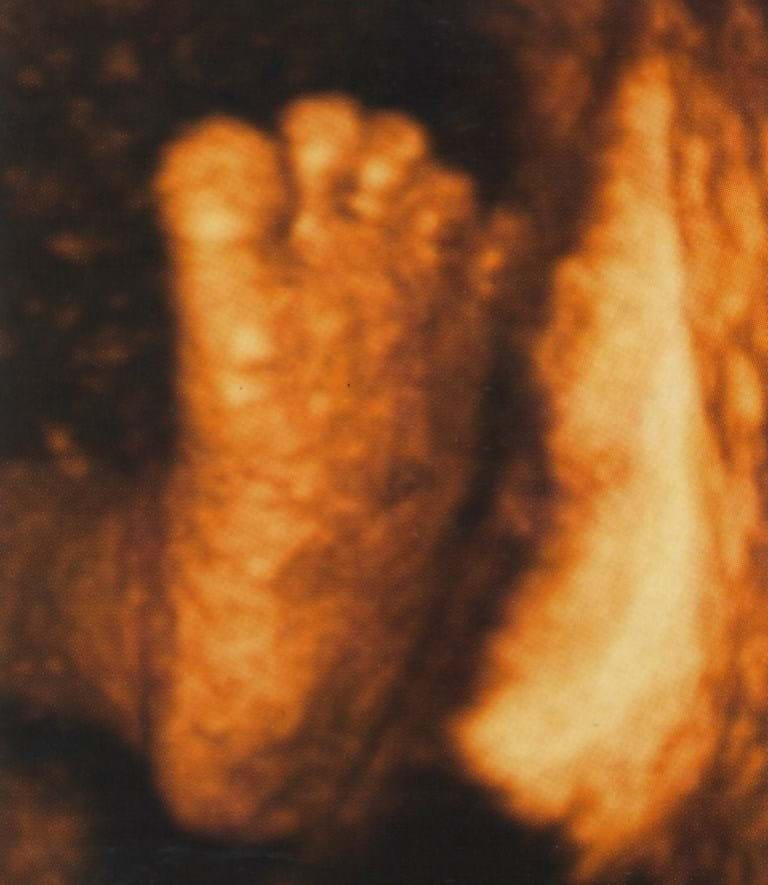

Pregnancy is an exciting time in your life. Dr Hardas is a skilled obstetrician with more than 20 years experience in managing high and low risk pregnancies. Dr Chen has trained in the largest tertiary obstetric hospitals in both Sydney and Melbourne managing both complex and low risk pregnancies with over 10 years of experience. Your obstetrician along with their team of expert midwives will provide care for you during your pregnancy. At the first consultation a detailed medical history will be taken and an ultrasound will be performed to confirm that your pregnancy is progressing normally. Routine antenatal blood tests including thyroid function, Vitamin D & iron levels will be ordered. A urine sample will be collected for analysis to check for protein, glucose and infection. Your obstetrician will discuss non-invasive testing for chromosomal disorders (such as Down Syndrome), They will arrange either a Nuchal Translucency (NT) ultrasound at about 12 weeks or a NIPS (non-invasive prenatal screen) which is performed after 10 weeks. You will be provided with general pregnancy advice such as nutrition, exercise and vitamin supplements. Booking into your preferred Maternity Unit as well as birth classes will be arranged. The frequency of visits is initially monthly and at each consultation you will have your blood pressure, weight and urine checked. Your obstetrician will perform an ultrasound at every consultation to check your baby's progress. |

Your frequency of visits will increase; every 2 weeks until 36 weeks and weekly thereafter. This is because most pregnancy complications, such as high blood pressure, occur in the later stages of pregnancy. Your obstetrician will perform an ultrasound at 28 weeks to ensure that your baby is growing well. You will have blood tests repeated to check for anaemia. A low vaginal swab is usually collected at 36 weeks gestation to screen for Group B Streptococcus. The 3rd Trimester care focuses on the health of the baby, in order to have it in the best possible condition before birth. We have various ways of assessing the baby's wellbeing including CTG, ultrasound for growth and fetal welfare studies. Finally, your birth plan and delivery options will be discussed at length to cater for you individual choices. |